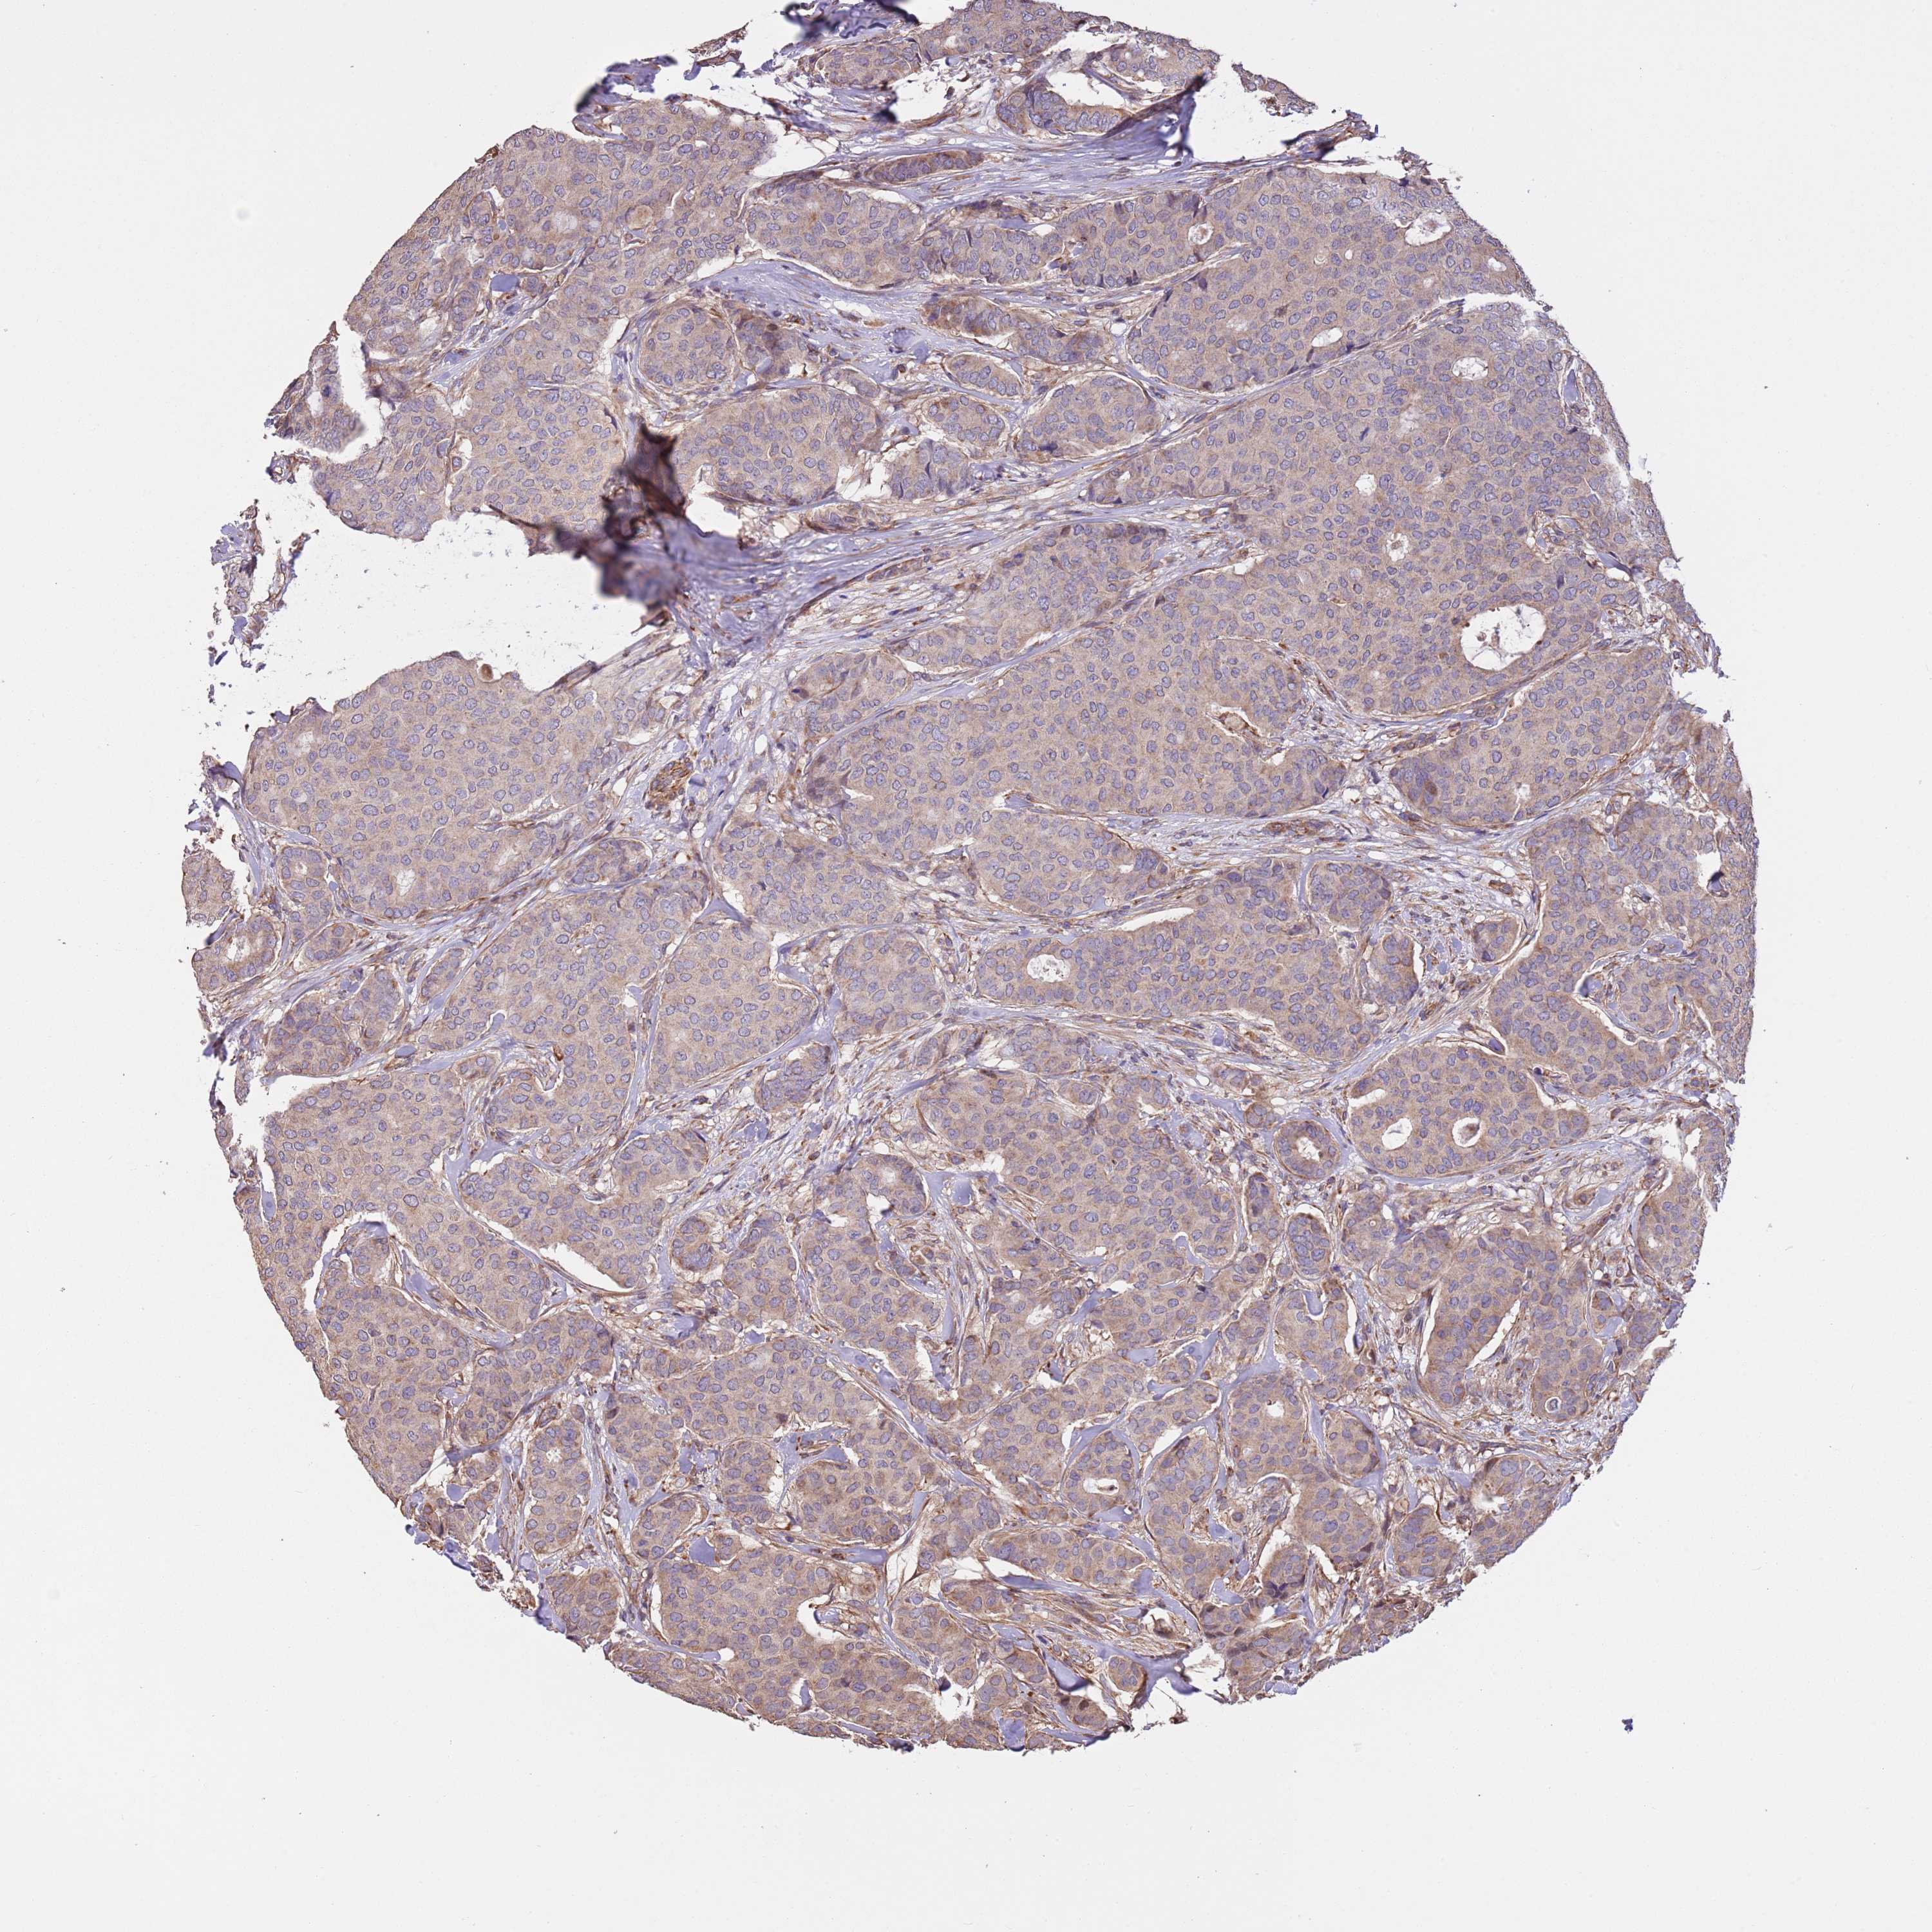

CANCER BREAST CANCER Show tissue menu

BRCA TCGA BRCA VALIDATION PROTEIN EXPRESSION

Breast cancer

Human cancer

Breast invasive carcinoma